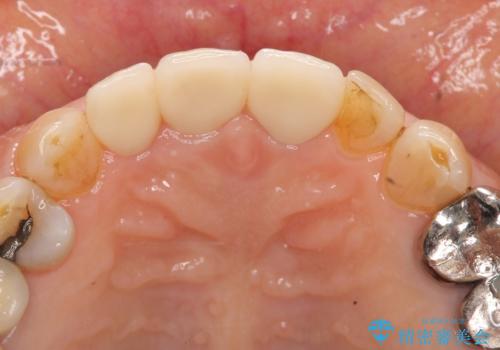

前歯の審美改善

- 40万円(仮歯・ファイバーコア・ジルコニアクラウン×3)費用は治療当時の料金となります

セラミック治療は外から見えるのはクラウンの色味・形態、歯肉の状態のみですが、X線撮影において現れるクラウンと歯牙の適合や、ファイバーコアの精度・根管充填の密度に、より長い予後を達成するための要素が含まれると考えます。